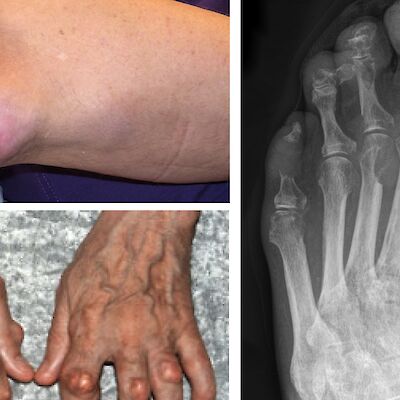

Hikinen mies poliisiasemalla – tapauksen ratkaisu Turvapaikanhakija tuotiin päivystykseen ambulanssilla. Roope Holopainen, Tanja Laukkala, Pekka Jylhä Tiede 23.4.2026 Kommentteja